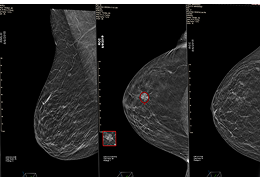

基于 4D Flow 深度学习的地标检测算法在 500 个 4D Flow MRI 和专家地标注释的数据库上进行了训练。对于每项研究,心脏放射科医生至少在一个时间点对 6 个标志物(LVA、RVA、AV、PV、MV、TV)进行了注释。对于所有 LVA、RVA、AV、PV、TV、MV 地标,我们使用具有 100,000 个 bootstrap 样本的 bootstrap 计算到地面实况的距离的中位数和中位数 P1 的 95%。对于所有检测到的地标,我们要求 P1 小于或等于 33mm。我们从这个测量中排除了我们的质量检测算法丢弃的地标。基于深度学习的 SSFP 分割算法在 1143 电影心脏 MRI 短轴系列上进行了训练。

不同地标的 P1 值为: LVA:8.4mm RVA:11.6mm MV:10.1mm PV:11.3mm TV:12mm AV:8.3mm 对于每个地标,检测率为: LVA:90% RVA:89% MV:91% PV:88% 电视:99% AV:88%